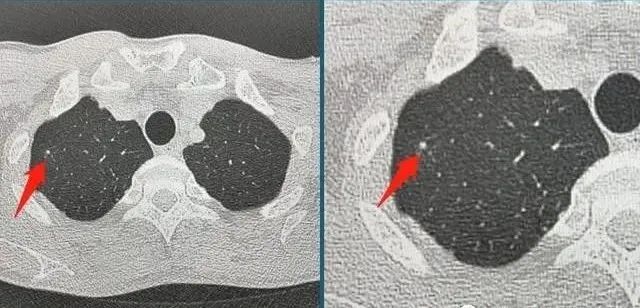

这种程度的创伤不会危及生命,经过一周的保守治疗后出院。后来,这位年轻人接受了CT扫描,在他的肺部留下了一个3毫米光滑的小结节:

这是一个良性的固体小结节,是由于血肿吸收不完全而形成的。没关系,没有必要定期随访.